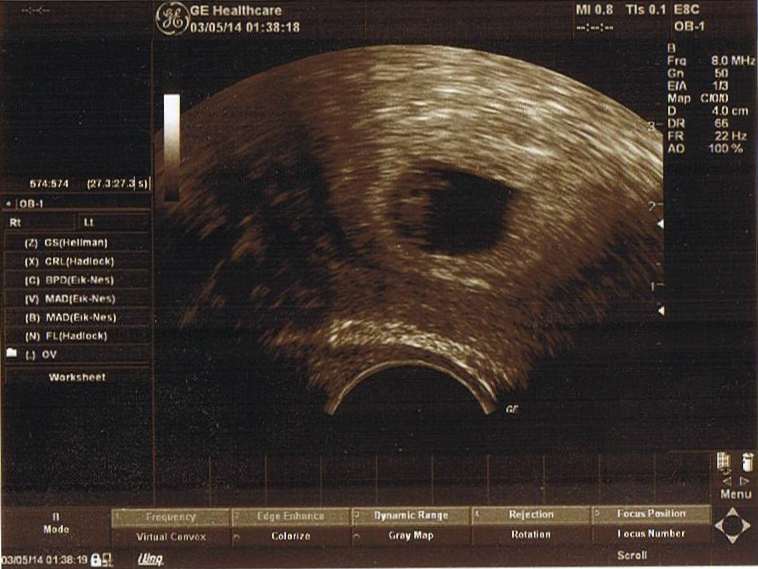

Первое УЗИ в 6+4 нед.

УЗИТест уже показал о наличии беременности, но так заболел живот и началась легкая мазня темно-бордового цвета, что пришлось ехать в legevakt /скорую помощь/. Сделали УЗИ и приободрили, повода для беспокойства не оказалось, всё в порядке. Взяли анализы, проверили - норма.